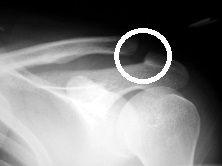

肩鎖関節の損傷(脱臼)は3型(tossy)に分けられ、Grade1:靱帯の軽度の損傷のみで捻挫と同様、レントゲンで明らかな関節のずれはない(写真1)。触診では肩鎖関節部の突出はなく軽度の圧痛がある。

写真1 肩鎖関節脱臼Grade1